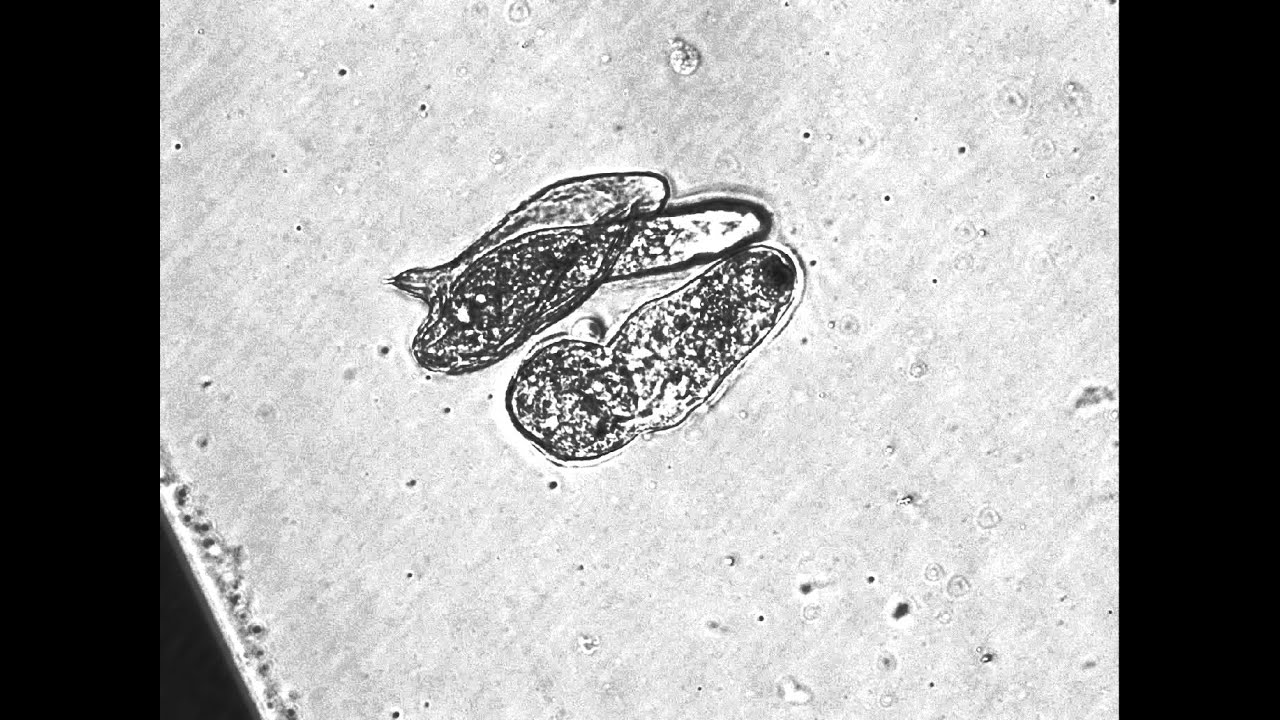

Скачать или смотреть Miracidia of S. mansoni in the ovum/egg.

Miracidia of S. mansoni in the ovum/egg.